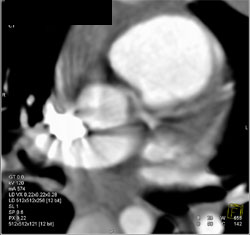

Diagnosis

Diseased LAD